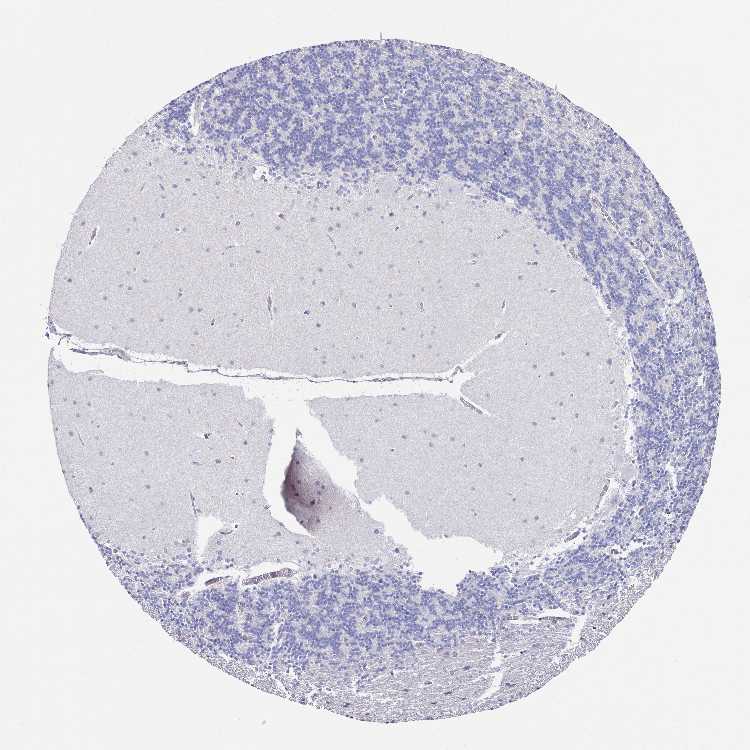

BRAIN CEREBELLUM Show tissue menu

CEREBELLUM - Expression summary

CEREBELLUM - Antibody stainingi

Antibody staining in the annotated cell types in the current human tissue is reported as not detected, low, medium, or high, based on conventional immunohistochemistry profiling in selected tissues. This score is based on the combination of the staining intensity and fraction of stained cells.

Each image is clickable and will lead to virtual microscopy that enables deeper exploration of all samples and also displays staining intensity scores, fraction scores and subcellular localization as well as patient and tissue information for each sample.

Antibody HPA048319Antibody CAB002602

Purkinje cells Not detectedLow

Cells in granular layer Not detectedNot detected

Cells in molecular layer Not detectedLow